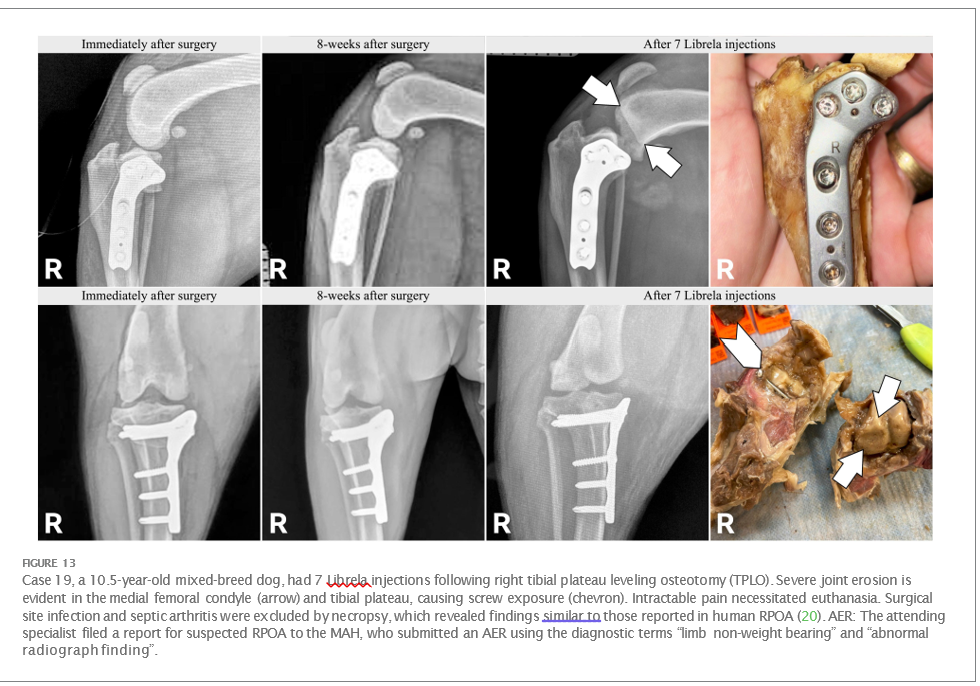

Clinical and radiographic characteristics are summarized in Table 2 and Figures 513. Mean ± SD number of Librela doses was 12.7 ± 9.5 (range 1–30), with a dose range of 0.4–0.76 mg/kg (mean 0.62 ± 0.08 mg/kg). Referral for investigation of suspected RPOA was made at least 6 months after Librela initiation in 13/19 cases. Eleven dogs (58%) received regular concurrent NSAIDs. The most frequently affected joint was the elbow (13/19 dogs, 68%), followed by the stifle and hock (two dogs each), and hip (one dog). Seven dogs (37%) sustained pathological fractures, and two (10.5%) had joint luxations. Two dogs with clinically normal hock joints before initiating Librela therapy developed severe non-index hock joint destruction after Librela treatment for elbow OA.

Histopathological examination of bone and synovial tissue from four dogs revealed no evidence of inflammatory arthropathy, tick- borne diseases, or neoplasia. A pathologist who was invited to compare their findings to those reported in a submitted article on human RPOA (20) commented that the pathological features were similar (21).

Interobserver agreement between diagnostic imaging specialists was substantial (κ = 0.68, 95% CI 0.4–0.97). Both specialists were very suspicious of a potential causal relationship between the observed pathology and Librela treatment in 68% of dogs (13/19). Furthermore, all 18 panelists (including the two diagnostic imagers) were very suspicious of a potential causal relationship between Librela treatment and the observed pathology.